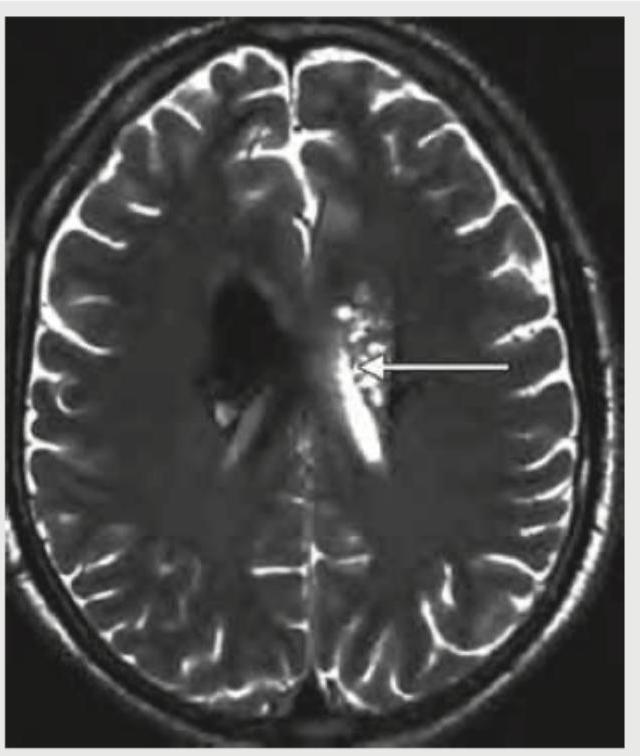

A 25-year-old AIDS patient who had stopped taking ART for 6 months presented with seizures and altered sensorium. MRI head of the patient shows:

Explanation: ***Toxoplasma*** - The MRI shows multiple **ring-enhancing lesions**, particularly in the basal ganglia and corticomedullary junction, which are characteristic of **Toxoplasma encephalitis** in an immunocompromised patient with AIDS. - The patient's history of **seizures** and **altered sensorium** in the context of advanced AIDS and cessation of ART strongly points towards an opportunistic infection like toxoplasmosis. *Cryptococcus infection* - Cryptococcal infections in AIDS patients frequently manifest as **meningitis** or **meningoencephalitis**, rather than focal brain lesions seen here. - While it can cause **cryptococcomas**, they are less common than Toxoplasma lesions and often appear as non-enhancing or minimally enhancing lesions, or associated with dilated Virchow-Robin spaces. *TB meningitis* - **Tuberculous meningitis** typically presents with meningeal enhancement, **basal exudates**, and sometimes **tuberculomas**. - While tuberculomas can be ring-enhancing, they are usually fewer in number and often associated with hydrocephalus, unlike the pattern seen in the image. *Herpes simplex encephalitis* - **Herpes simplex encephalitis (HSE)** characteristically affects the **temporal and frontal lobes**, leading to edema and sometimes hemorrhagic changes. - The lesions seen in the image are more multifocal and less restricted to the typical HSE regions.